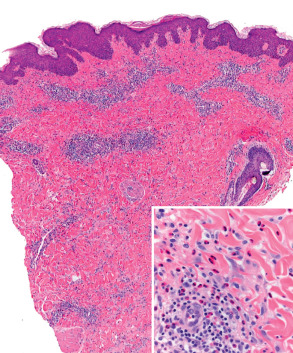

Pathology

Skin biopsy specimens reveal nonspecific findings. Epidermal changes vary from modest spongiosis to acanthosis with hyperkeratosis and parakeratosis, depending upon the stage of the disease. The dermis shows a nonspecific perivascular lymphocytic infiltrate with a variable degree of dermal edema and a variable number of neutrophils or eosinophils. Early lesions may resemble arthropod bite reactions, with a deeper dermal infiltrate and an absence of epidermal changes ( Fig. 27.6 ). The histologic correlate of microvesiculation is severe epidermal spongiosis and/or dermal edema. Direct IF reveals no relevant abnormalities and indirect IF is negative. Routine laboratory evaluation is normal.